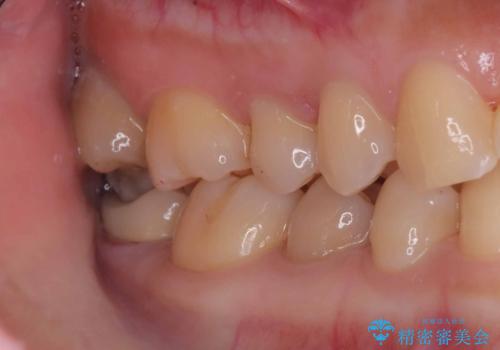

- 税込176,000円(オールセラミッククラウン121,000円+仮歯11,000円+VPT44,000円)費用は治療当時の料金となります

虫歯が神経まで達していましたが、術前の検査でVPTの適応と診断をしていたので、ラバーダムシートを装着しVPTを行いました。

経過も良好で、痛みも無く神経を残すことが出来ました。